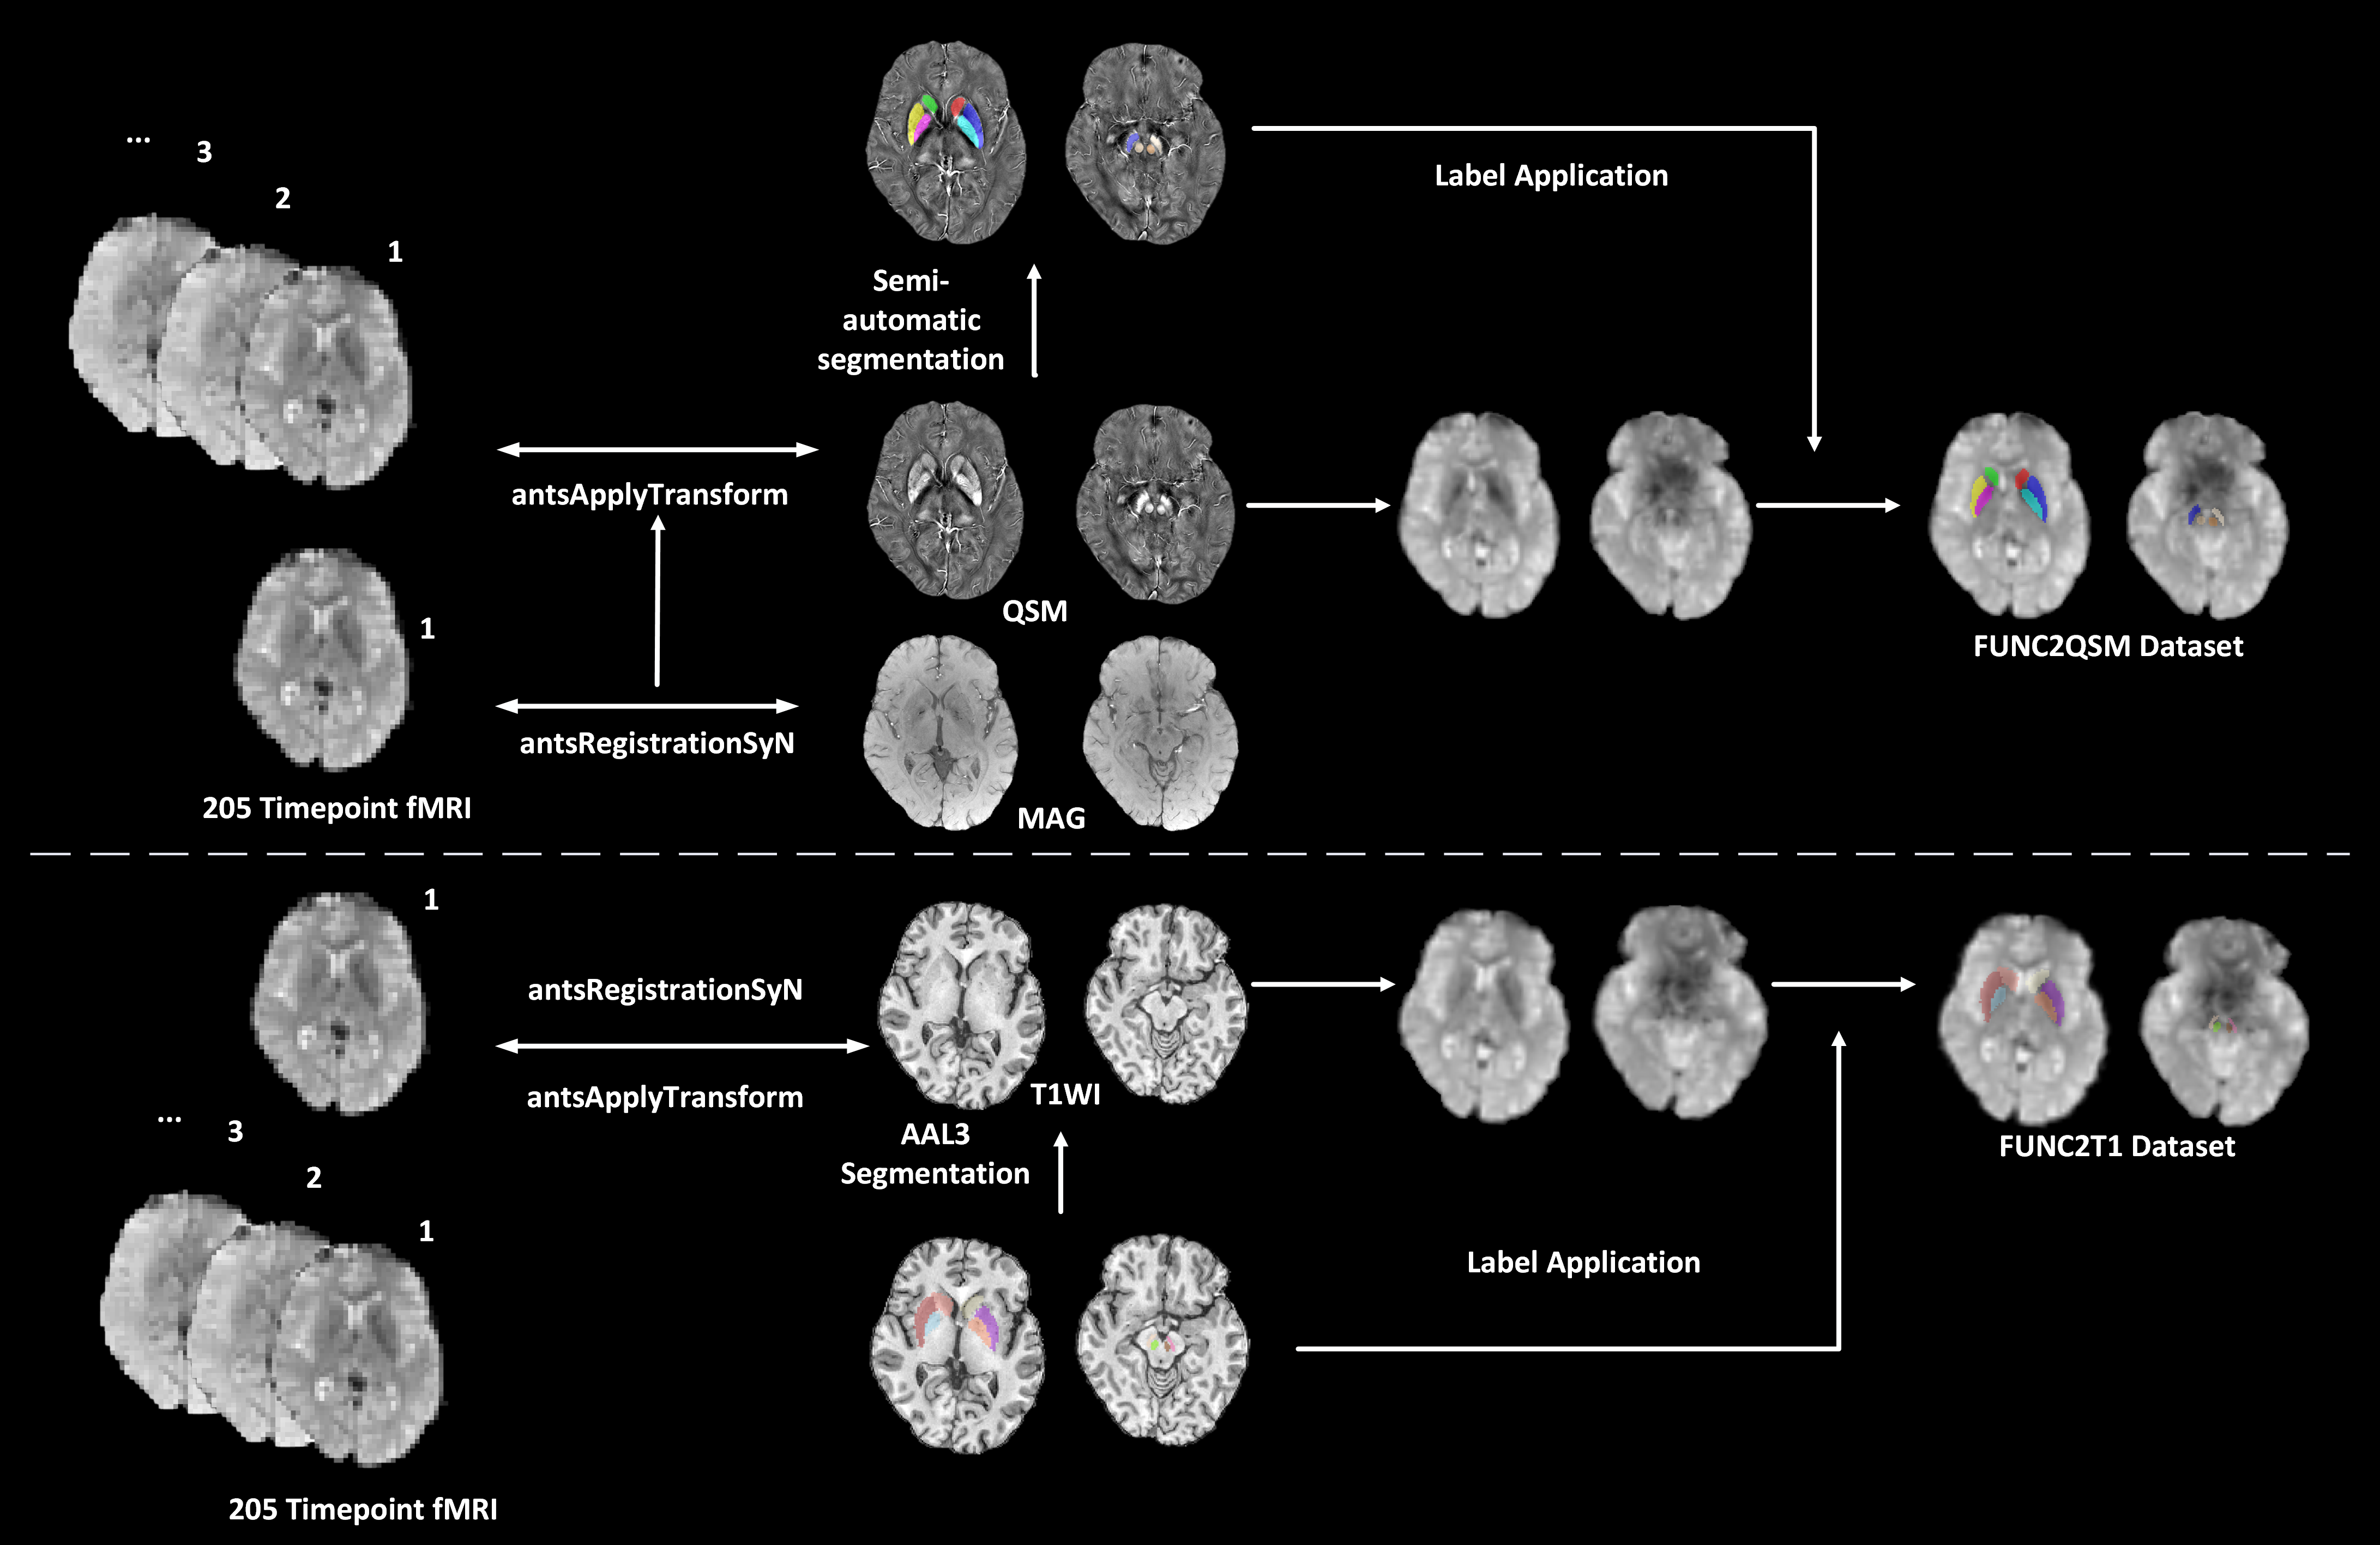

Method: A total of 321 participants (148 patients with Parkinson’s Disease and 173 normal controls) were enrolled. We performed cross-modal registration at the individual level for rs-fMRI to QSM (FUNC2QSM) and T1WI (FUNC2T1), respectively [figure2]. The consistency and accuracy of resting state functional connectivity (RSFC) measurements in two registration approaches were assessed by intraclass correlation coefficient and mutual information. Bootstrap analysis was performed to validate the stability of the RSFC differences between Parkinson’s disease and normal controls. RSFC-based machine learning models were constructed for Parkinson’s disease classification, using both default hyperparameters and optimized hyperparameters (RandomizedSearchCV with 5-fold cross-validation).

figure2